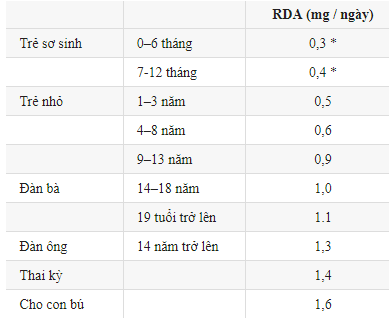

Những giá trị trên đại diện cho lượng hàng ngày đủ để đáp ứng yêu cầu của hầu hết mọi người.